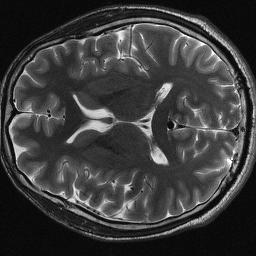

Magnetic resonance imaging serves as an essential tool for clinical diagnosis. However, it suffers from a long acquisition time. The utilization of deep learning, especially the deep generative models, offers aggressive acceleration and better reconstruction in magnetic resonance imaging. Nevertheless, learning the data distribution as prior knowledge and reconstructing the image from limited data remains challenging. In this work, we propose a novel Hankel-k-space generative model (HKGM), which can generate samples from a training set of as little as one k-space data. At the prior learning stage, we first construct a large Hankel matrix from k-space data, then extract multiple structured k-space patches from the large Hankel matrix to capture the internal distribution among different patches. Extracting patches from a Hankel matrix enables the generative model to be learned from redundant and low-rank data space. At the iterative reconstruction stage, it is observed that the desired solution obeys the learned prior knowledge. The intermediate reconstruction solution is updated by taking it as the input of the generative model. The updated result is then alternatively operated by imposing low-rank penalty on its Hankel matrix and data consistency con-strain on the measurement data. Experimental results confirmed that the internal statistics of patches within a single k-space data carry enough information for learning a powerful generative model and provide state-of-the-art reconstruction.